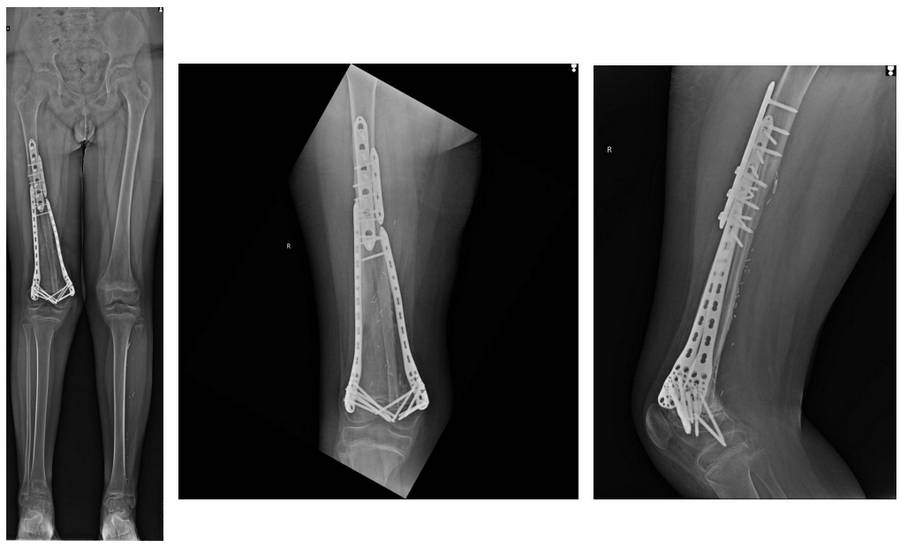

Ameliyat Sonrası: Röntgende geri kazanılan kemik dokusunun vaskülerize fibula ile kombine edildikten sonra proksimal ve distalden çift plak ile fiksasyonu görülmekte